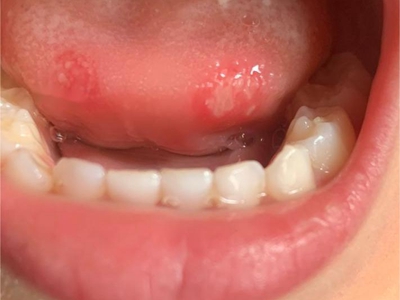

小儿口疮下嘴唇里面有三个白色溃疡点图

小儿口疮患儿下嘴唇内侧会出现数个白色溃疡面,为不规则形状,直径较小,但有融合趋势,周围黏膜发红,提示炎症反应较重,需及时治疗。